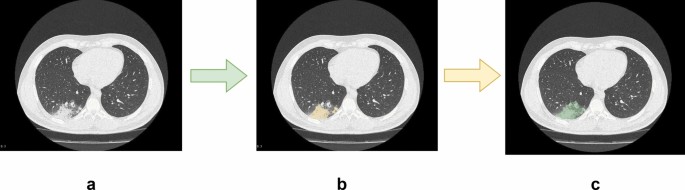

CT image segmentation

Figure 2a shows the original CT image slice. Figure 2b displays the result after automatic segmentation using the nnU-Net, where it is evident that the model can accurately identify the lesion area. Figure 2c is the adjusted result by a radiologist based on image (b).

Unlike X-ray films, CT scans consist of multiple slices, making ROI delineation more time-consuming. According to our statistics, it takes a radiologist approximately 15 min to independently delineate the ROI of a lung CT scan. However, if the nnU-Net model is used for initial segmentation, and then a radiologist makes adjustments based on that, the time is reduced to 3 min. This significantly improves the efficiency of image segmentation. In terms of segmentation accuracy, since the radiologist further adjusts the ROI, the final segmentation accuracy is greatly ensured.